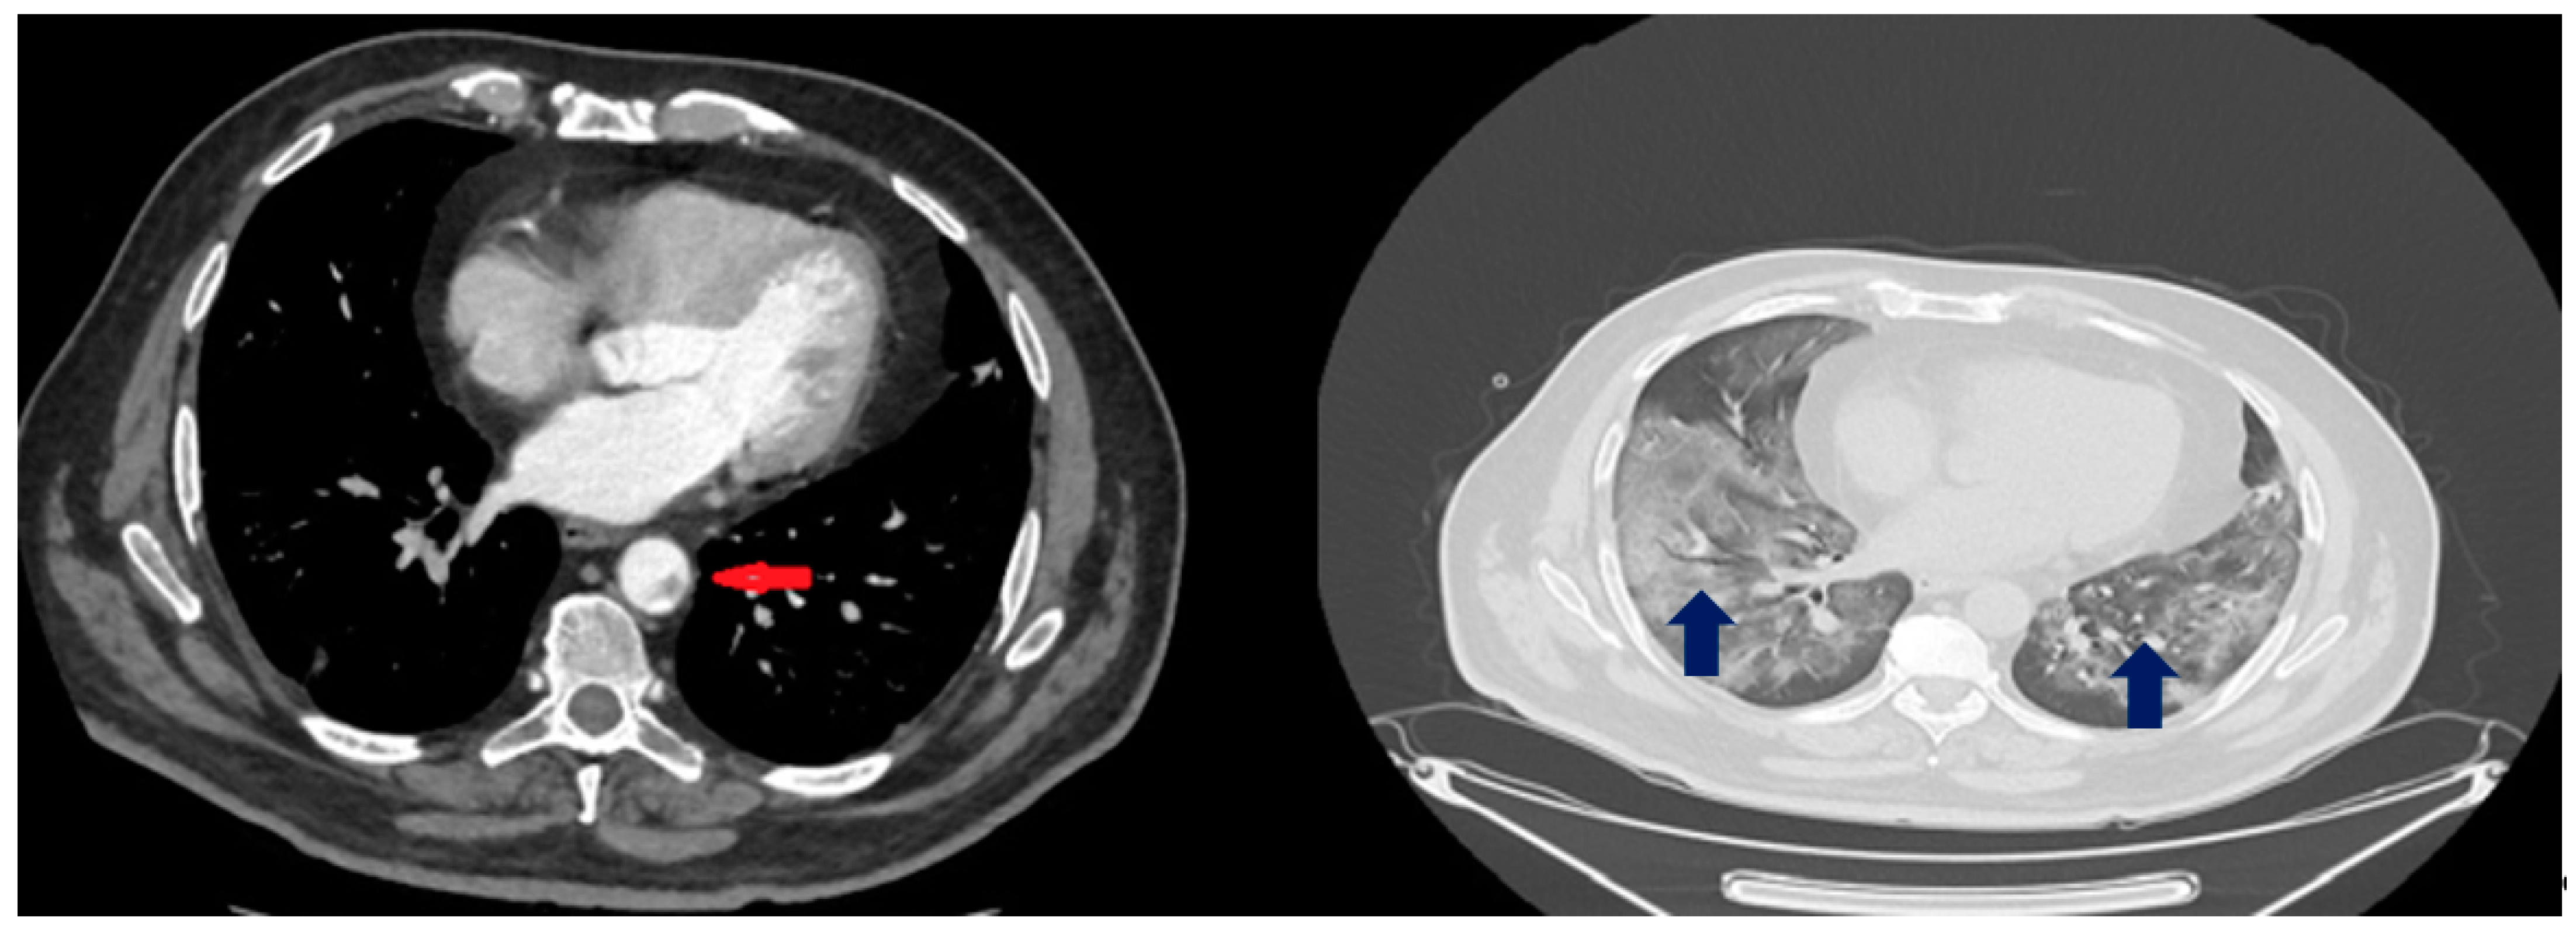

| Day 6 | Blood exams: 23,000 WBCs, LDH 1892 U/L, d-dimers 4.3 mg/L CTPA: Bilateral ground glass opacities, no evidence of pulmonary embolism, thrombi up to 5 mm in the thoracic aorta Abdominal and pelvic CT scan: Splenic infarct, thrombosis of splenic artery and vein, renal infarct at the left lower lobe. Enoxaparine at therapeutic dose (8.000 IU twice daily), acetylsalicylic acid 80 mg |